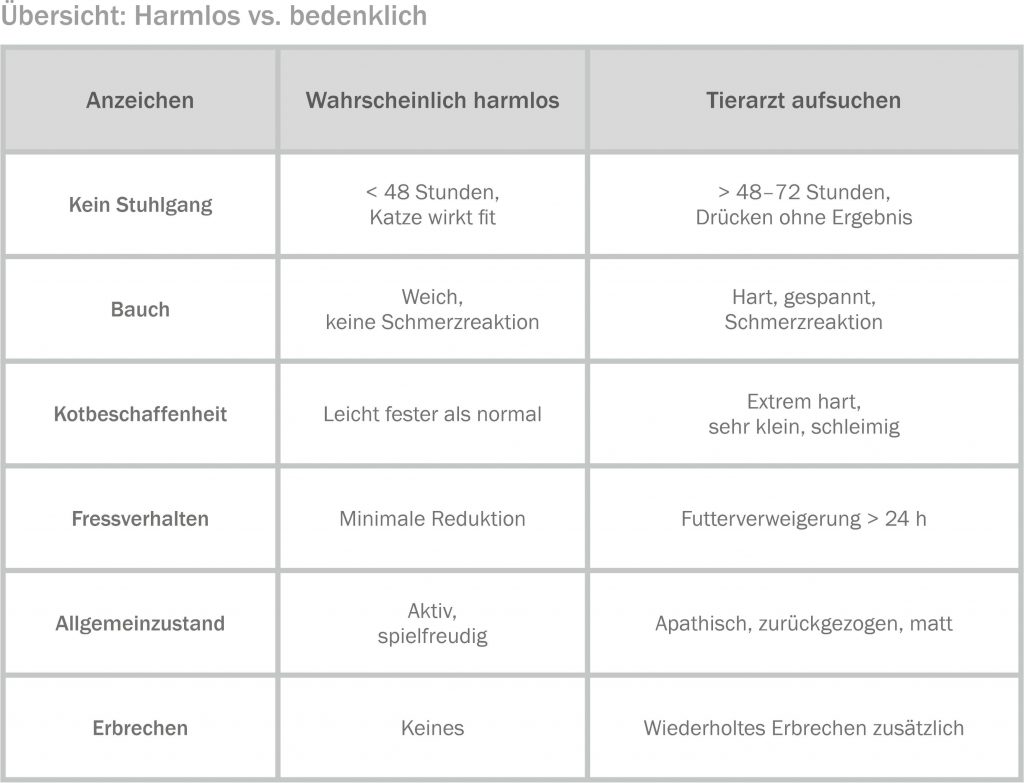

Diese Frage lässt sich eindeutig beantworten: Lieber einmal zu früh als einmal zu spät! Sobald Begleitsymptome auftreten oder die Verstopfung hartnäckig anhält, solltest du deine Katze einem Tierarzt vorstellen. Die folgende Checkliste gibt dir Orientierung.

- Kein Stuhlgang seit mehr als 48–72 Stunden trotz Maßnahmen zu Hause

- Mehrfaches erfolgloses Pressen im Katzenklo

- Erbrechen (mehr als einmal, oder schleimig/gallig)

- Harter, gespannter Bauch oder Schmerzreaktion beim Berühren

- Futterverweigerung über mehr als einen Tag

- Apathie und Rückzug, die sich über Stunden hinweg verschlechtern

- Wiederholte Verstopfungsepisoden innerhalb eines Monats

- Katze ist älter als zehn Jahre und zeigt erstmals Verdauungsprobleme